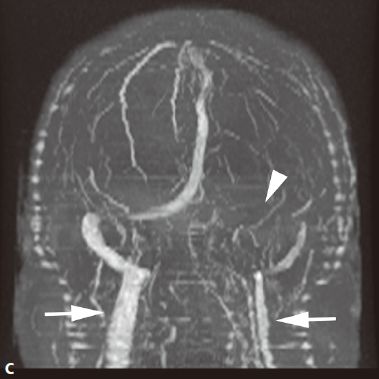

- 动静脉畸形(AVM ): 迂曲扩张的 供血动 脉与 引流静脉 之间无正常毛细血管,而是通过 畸形的血管 袢 直接相通,形成 异常的血管团 。畸形血管易破裂出血,由于动静脉短路,周围脑组织因缺血而发生萎缩,称为“盗血”现象。多见于大脑中动脉分布的脑皮质,也可发生于侧脑室脉络丛、硬脑膜、软脑膜、小脑及脑干。主要临表:出血(蛛网膜下腔出血及脑实质出血)、癫痫、头痛。

- 脑血管造影(DSA)及CTA :是诊断AVM的可靠办法,可以显示动静脉畸形血管团、明显增粗迂曲的供血动脉及引流静脉。

- CT检查:平扫表现为局灶性团块状或点状混杂密度区、形态不规则,边界不清,可见钙化;增强扫描病灶区呈蚯蚓状、团块状强化,有时可见点线状迂曲的扩张血管影,其周围可见粗大的供血动脉及迂曲扩张的引流静脉。可出现局限性脑萎缩,无占位效应、无脑水肿。

- MRI检查:畸形血管团由于流空效应,在T1WI及T2WI上均无信号,供血动脉表现为低或无信号。不伴有出血时,病灶无占位效应及周围水肿,邻近脑组织呈萎缩。